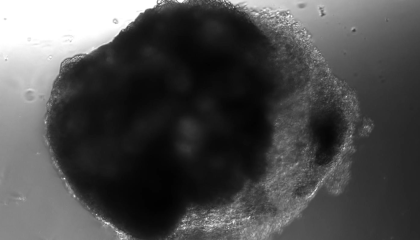

2021年5月,維也納一家研究所通過在體外利用化學物質誘導多功能幹細胞製造了許多芝麻大小的微型心室,第五天,這些小心臟開始抽搐,第七天,它們開始搏動。儘管現有的心臟再生手段尚不足以應用於臨牀,但無論是體內還是體外再生,看上去均有所突破。

▍人工小心臟的搏動